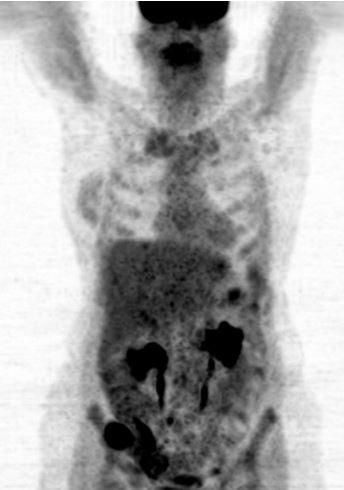

Intrahepatiske echinococcus multilocularis lesjoner som falsk postitive funn i pasient med adenocarsinom i jejunum.

PET